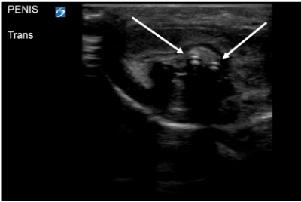

with a palpable foreign body, but nothing was visualized at the urethral meatus. Plain radiography was interpreted as normal with no visualized foreign body. Lab work and urinalysis were also normal. Clinicians using POCUS were able to visualize a linear hyperechoic object within the urethra (Image 1). Urology was consulted and took the patient to the operating room (OR) for removal with cystoscopy. In the OR a rolled-up piece of plastic was identified three centimeters into the urethra and was successfully removed. The patient was discharged without complication the following day.

Bedside ultrasound identified three linear hyperechoic objects in the bladder (Image 2), with none seen in the urethra. This was followed by a CT, which confirmed the findings; three foreign bodies were retained in the bladder. Urology was consulted, and the patient was admitted to the hospital. Urology performed a cystoscopy with open cystotomy, removed the foreign bodies, and placed a Jackson-Pratt (JP) drain and Foley catheter. The hospital course was complicated by traumatic damage to the urethra, small extravasation from the bladder, and Enterococcus faecalis urinary tract infection. Infectious disease and psychiatry were consulted. The patient completed a course of antibiotics, had the JP drain and Foley catheter removed, and was discharged on hospital day 20.

a braided USB-type cord without hub attachments into his urethra. He had similarly inserted foreign bodies into his urethra in the past but stated, “This is the first time I couldn’t get it out.” On arrival the patient was in no acute distress. Genitourinary exam was significant for a single, braided cord protruding from the urethra. Neither the patient nor the emergency physicians were able to extract the cord with gentle traction. Using POCUS, the clinicians identified the cord in the bladder, as well as evidence that the cord had looped within the urethra (Image 3). Urology was consulted, and a urologist evaluated the patient at bedside. The patient